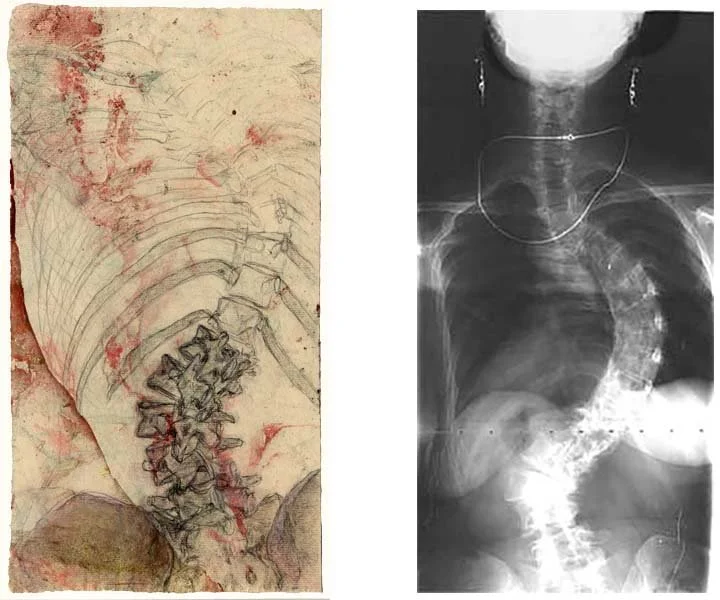

As I got further into my project, I felt the need for better source materials, and I began to collaborate with orthopedic surgeons and radiologists to have medical images made for the purpose of art. It was exciting to art-direct my first x-ray! Keeping my earrings and gold chain on (instead of, as usually happens, being made to take off everything metal) made me feel triumphant, and made the x-ray image more personal. Working with doctors as an artist and fellow professional, I felt respected and seen in a way I never had as a patient.

Soon I was searching for a more three-dimensional medical imaging technology, and in 2000, thanks to Dr. Andrew Litt at NYU School of Medicine, I had a cutting-edge spiral CT scan with 3D volume rendering. It was a stunning experience to see my skeleton appear in 3D on a computer screen, after all the years I had spent trying to visualize it. (In 2008, when the technology could capture an even greater level of detail, I had a second spiral CT scan.)

I drew my figure from the outside first, in poses that came from my own vocabulary of movement, then made studies of the skeleton in that pose, using my 3D scan films and the human skeleton as references. Once I had come to know the pose from inside and out, I put the elements together in a drawing that made the skeleton visible through the transparent surface of the skin.